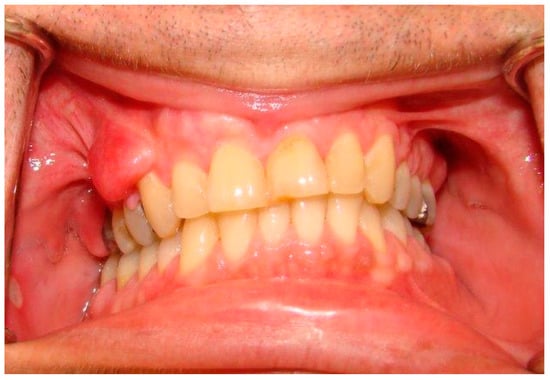

| Oral soft tissue | Prominent lingual papillae (50% cases); Mucosal and gingival neurofibromas * (25% of cases): mostly the tongue, followed by buccal mucosa, lips, and gingiva, and less commonly the palate, the floor of the mouth, the major salivary glands and the pharynx; Macroglossia in relation to plexiform neurofibromas arising inside the tongue; Melanin pigmentation of the gingiva (rare); Gingivitis or periodontitis in relation to oral neurofibromas prohibiting a proper oral hygiene. |